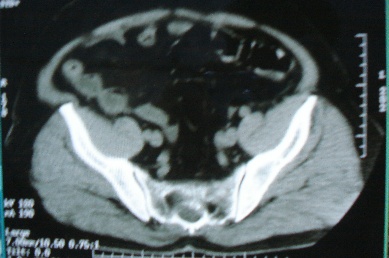

以下是引用zhangzhongshou在2007-6-17 11:53:00的发言:[br]骶管囊肿可能性大,建议mri检查。

以下是引用jinguoji在2007-6-17 14:53:00的发言:[br]骨质未见确切破坏,考虑骶管囊肿可能性大,建议mri检查。